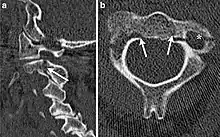

CT scan of hangman's fracture